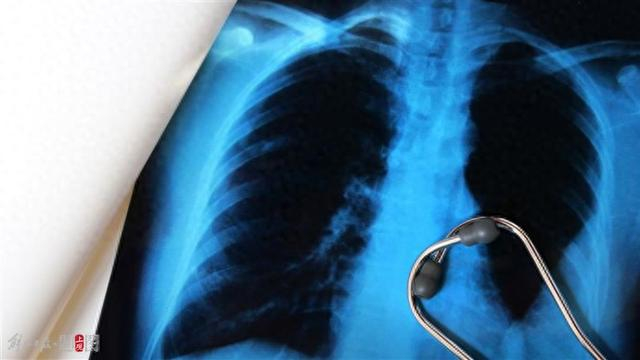

检查发现其血氧饱和度已低至85%

肺泡吸入羽绒导致的过敏性肺炎

俗称“羽绒肺”

“羽绒肺”有哪些典型表现,一旦发作就要引起我们重视?陈丹表示,患病早期,患者会持续性干咳、胸闷、乏力,易被误认为普通感冒或支气管炎而忽视,未能在第一时间得到有效治疗,导致病情恶化。“若持续暴露,可能出现呼吸困难、血氧饱和度下降至85%以下,甚至呼吸衰竭。”